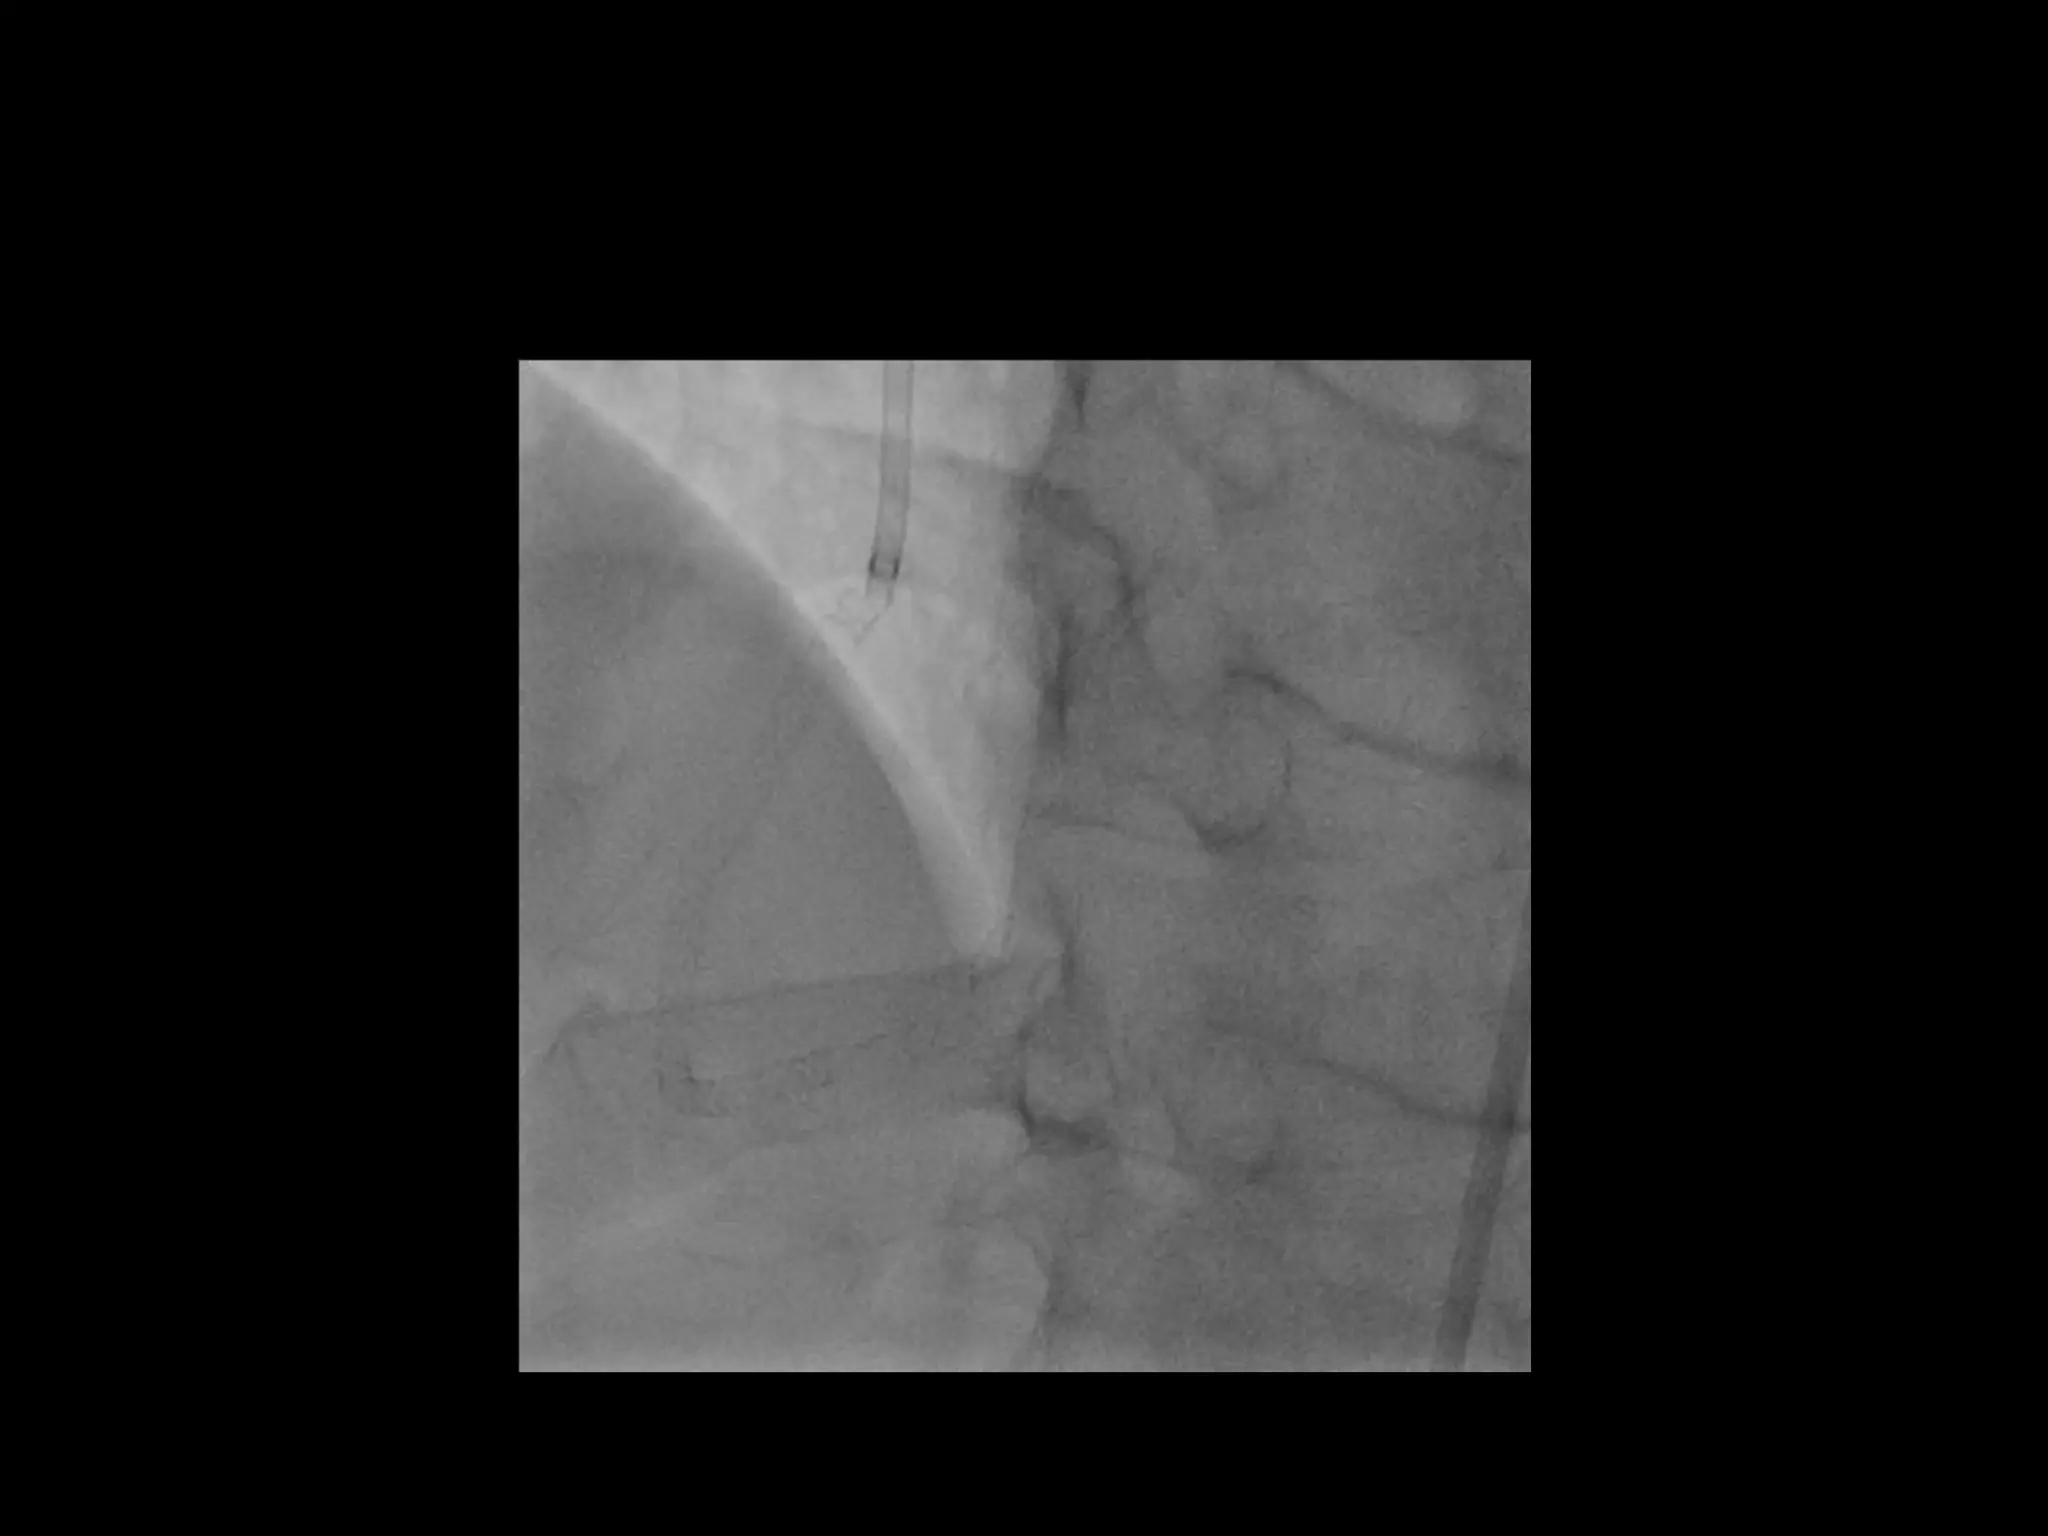

This document provides guidance on evaluating the feasibility of percutaneous coronary intervention (PCI) for a chronic total occlusion (CTO). Key factors to consider include: the patient's tolerance for a long procedure, contrast load, and radiation exposure; the CTO's proximal cap ambiguity, length, distal landing zone, and presence of interventional collaterals; and ensuring good quality angiography. With adequate planning and use of appropriate CTO techniques, feasibility is nearly always present for symptomatic patients. Success rates of CTO-PCI are reported to be 94% when using a planned approach.